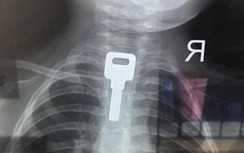

Các bác sĩ Khoa Cấp cứu, BV Trung ương Quân đội đã tiếp nhận 1 cụ bà 90 tuổi, ở Hà Nội được đưa đến trong tình trạng nguy kịch, khó thở thanh quản, thở rít, tím tái, kích thích vì dị vật mắc vùng cổ. Ngay lập tức bệnh nhân được thở oxy dòng cao qua Canun mũi, thuốc giãn phế quản và tiến hành chụp cắt lớp vi tính xác định vị trí dị vật. Kết quả phát hiện bệnh nhân có dị vật thanh quản ngay sát dây thanh, gây tắc gần hoàn toàn đường thở.

Theo người nhà, trước nhập viện, cụ bà được người nhà cho ăn kẹo và quả hồng xiêm. Sau 1 ngày, thì xuất hiện khó thở tăng dần, thở rít, nên cụ bà được gia đình đưa đến cơ sở y tế và được chẩn đoán mắc dị vật đường thở trên người bệnh cao tuổi.